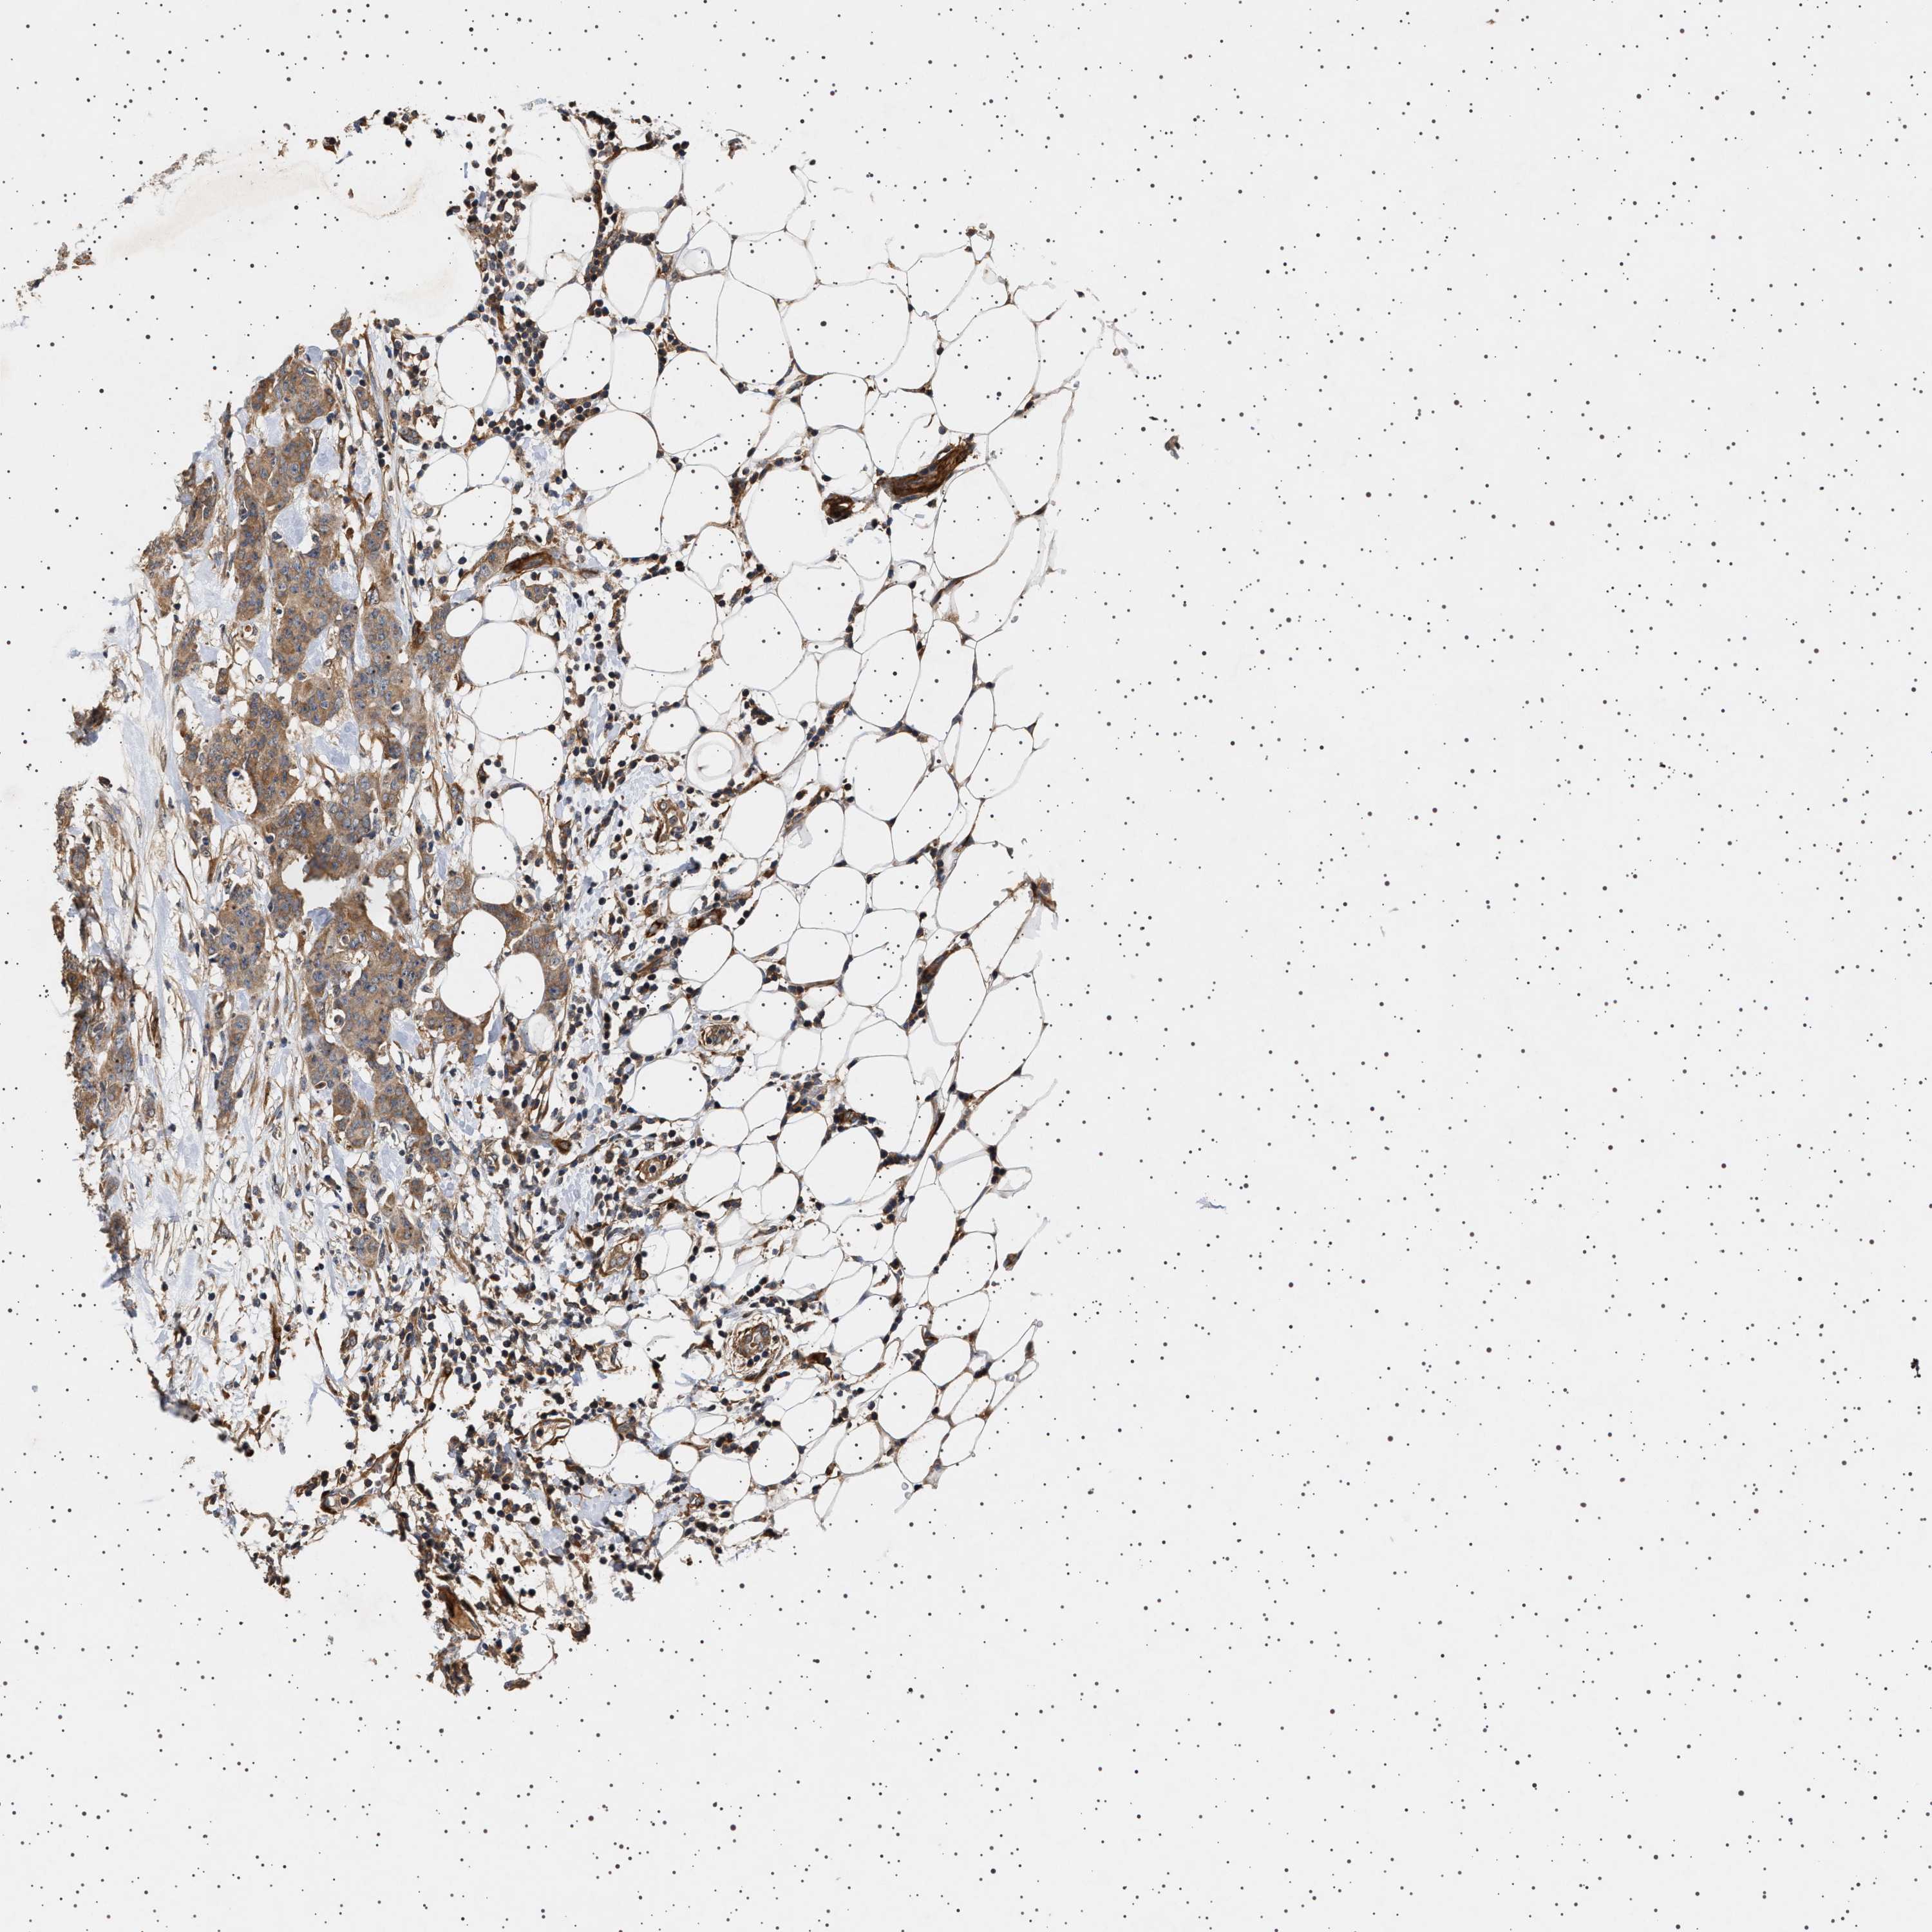

BRCA TCGA BRCA VALIDATION PROTEIN EXPRESSION